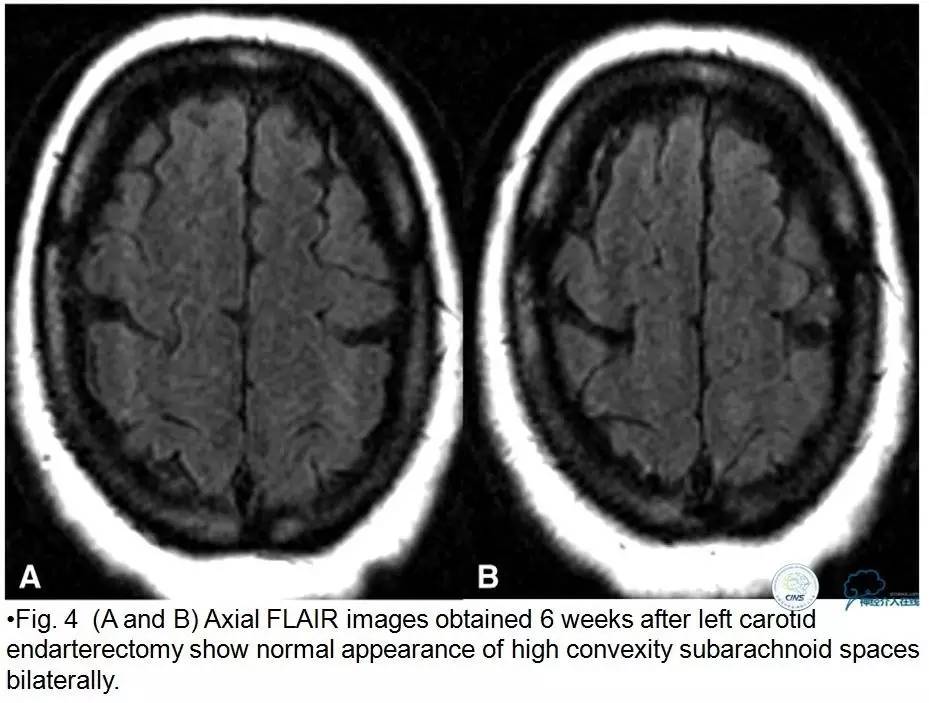

▼2015-06-05颅脑MRI

▼颅脑CT

▼2015-06-13颅脑CT

患者症状稳定,遗留有失语及右侧肢体活动不灵。